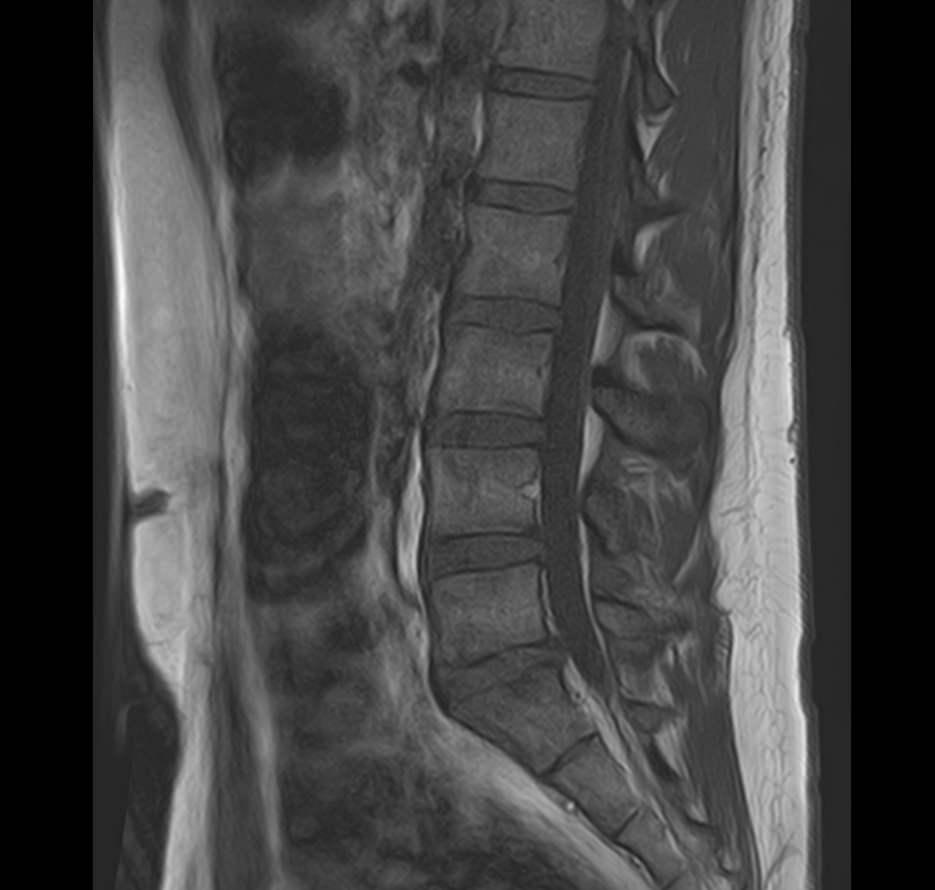

Наиболее точным и эффективным способом диагностики причин появления болей в нижней части спины является МРТ пояснично-крестцового отдела позвоночника. С помощью данного метода можно оценить состояние всех анатомических структур позвоночного столба на исследуемом уровне, безошибочно выявить происхождение болевого синдрома и назначить своевременное лечение.

В клинике «Доступная медицина» диагностика патологии нижней части спины осуществляется на высокотехнологичном оборудовании – новейшем высокопольном томографе TOSHIBA VANTAGE TITAN 1,5 Тесла, который обеспечивает высочайшее качество изображений, точность и достоверность полученных данных. Магнитно-резонансная томография осуществляется без применения ионизирующего излучения, поэтому является безопасным методом обследования и может применяться неоднократно.

Многим пациентам интересно, что показывает МРТ пояснично-крестцового отдела. Высокая детальность получаемых с помощью МР-диагностики изображений позволяет с точностью выявить следующие заболевания, локализующиеся в области поясничного отдела позвоночника:

• протрузии и грыжи межпозвонковых дисков;

• дегенеративные заболевания: остеохондроз, спондилез, спондилоартроз;

• последствия перенесенных травм, такие как компрессионные переломы, подвывихи и смещения позвонков;

• новообразования первичного и вторичного генеза;

воспалительные и деструктивные изменения позвонков и окружающих мягких тканей.